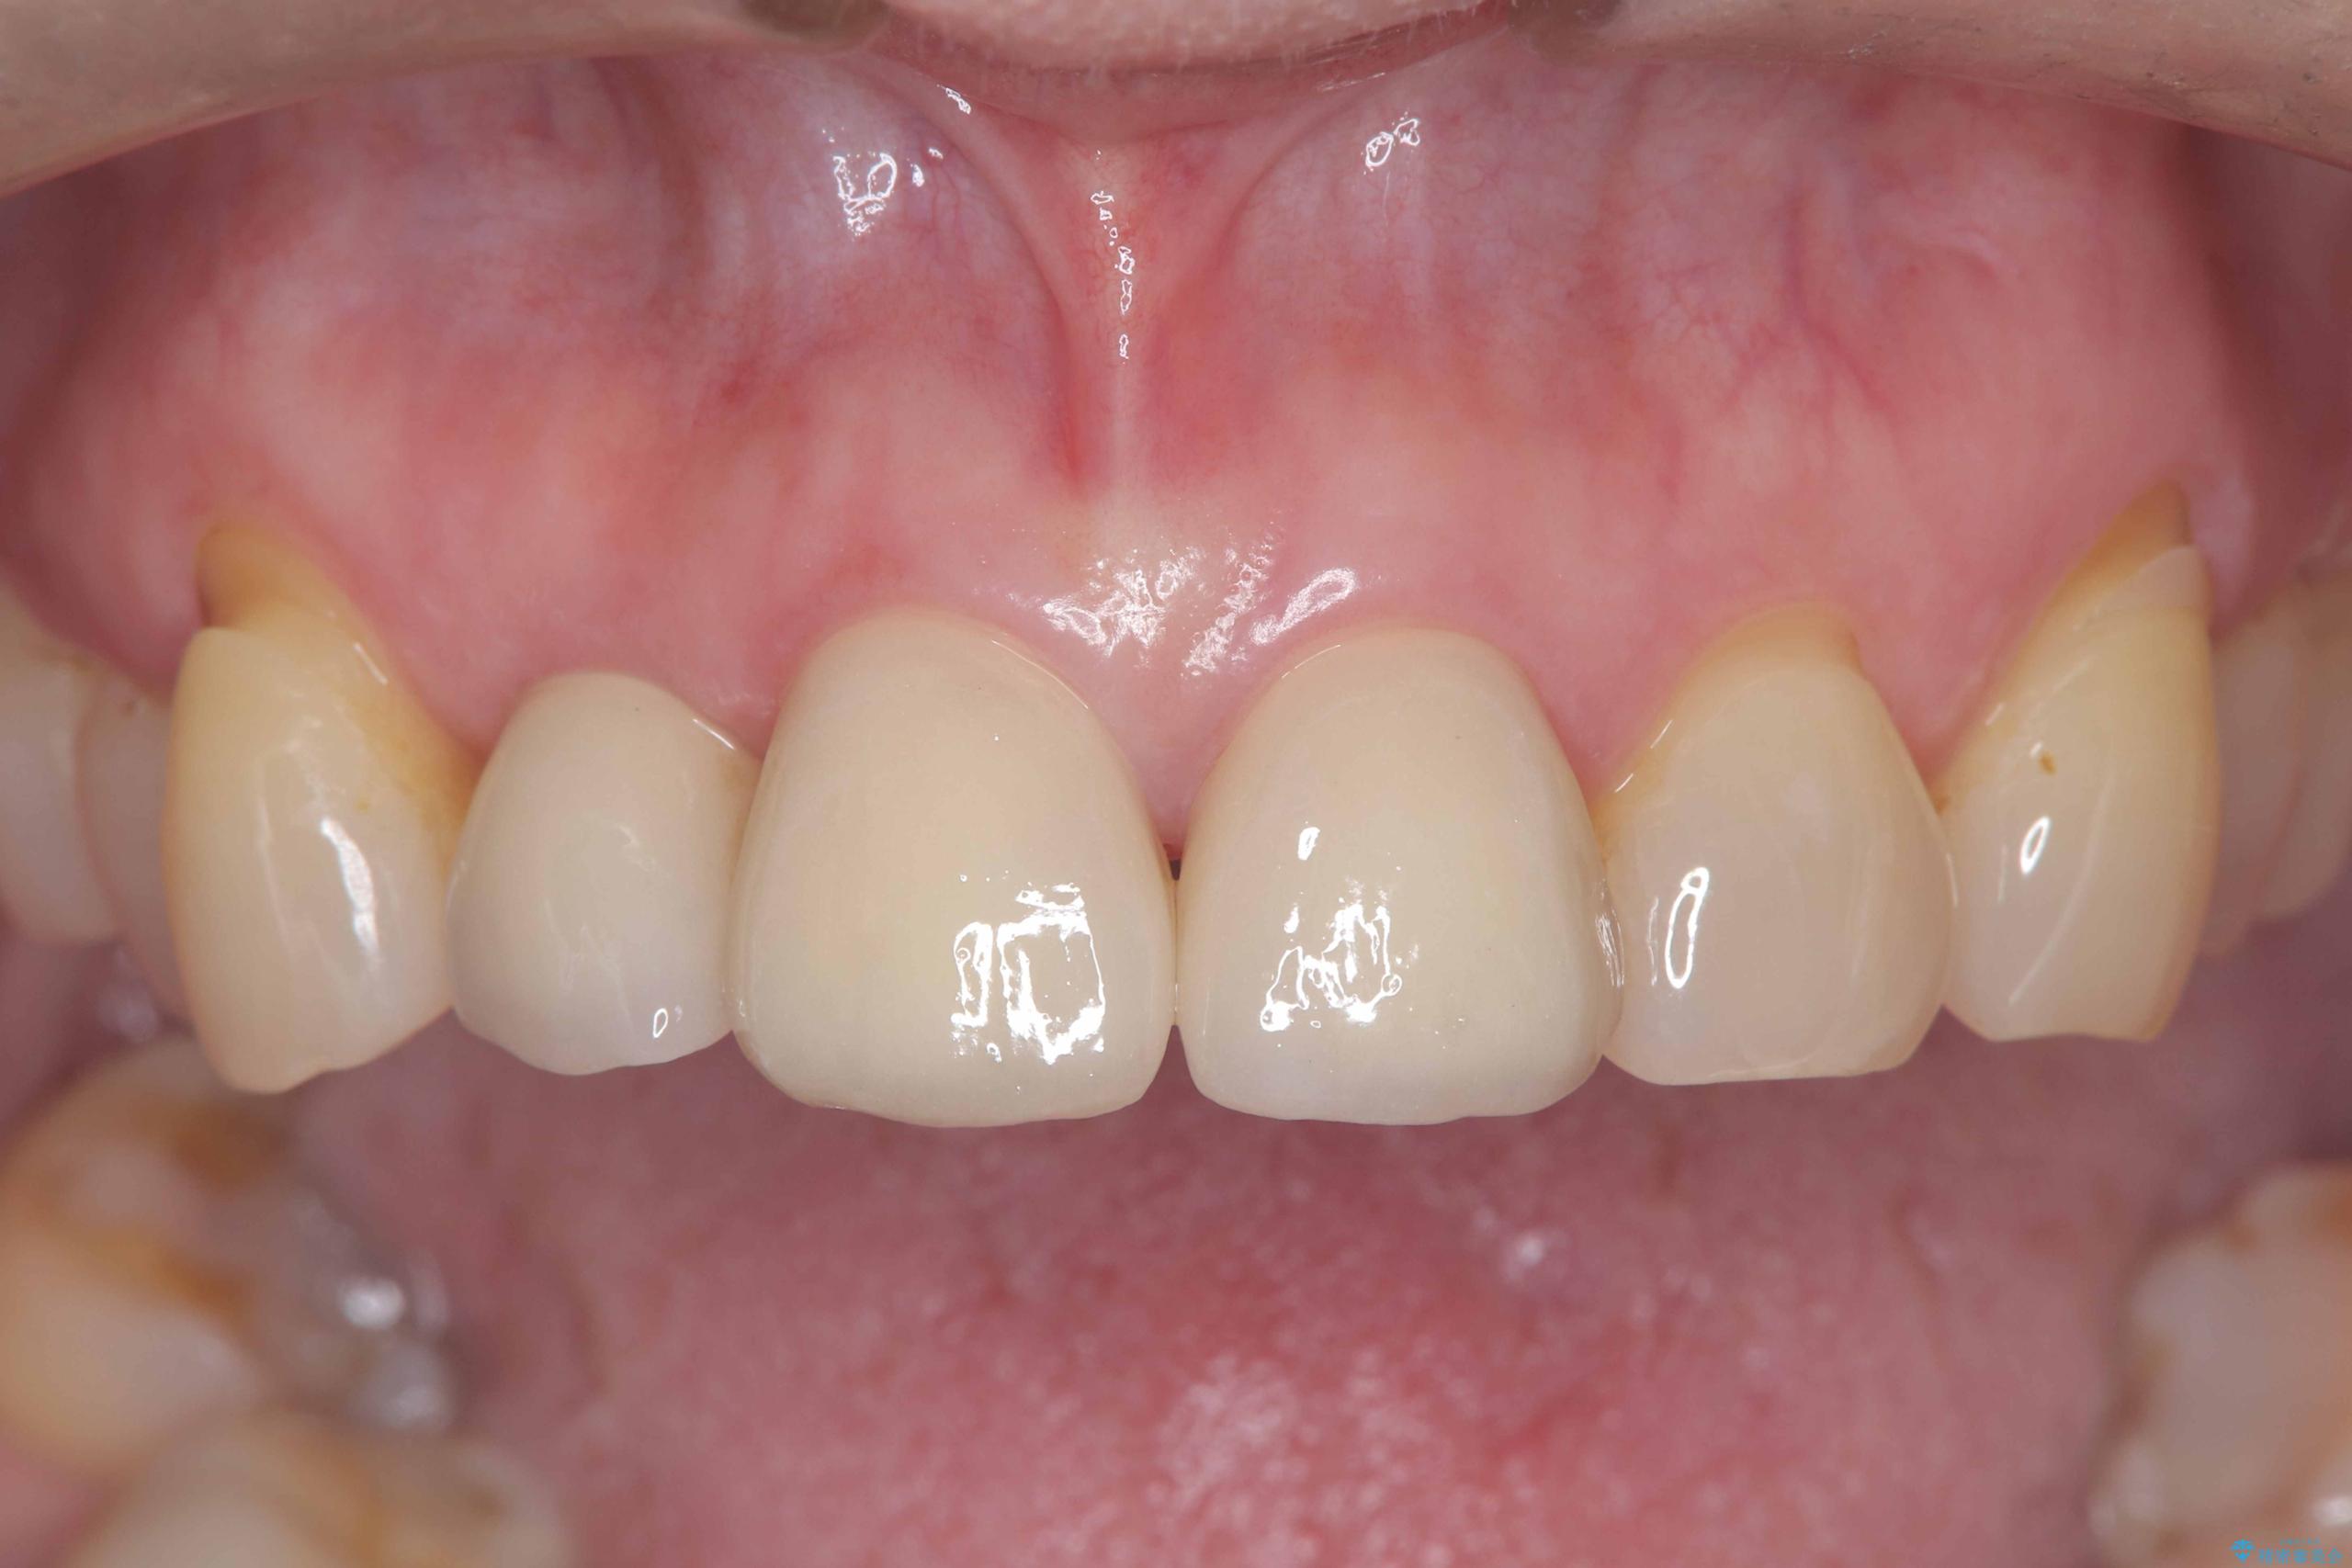

そのため今回は、右上2番を抜歯し、右上1番および左上1番をオールセラミッククラウンで審美的に修復しました。

矯正によって歯並びや咬み合わせを整えた後、必要に応じて歯の形や色を整えるためにホワイトニングやセラミック治療を行うことで、より自然で美しい仕上がりが期待できます。

治療期間も短く、抜歯からわずか3か月でオールセラミッククラウンを装着することができます。

また、オペ当日には仮歯まで装着するため、見た目を気にせず普段通りの生活を送ることができます。